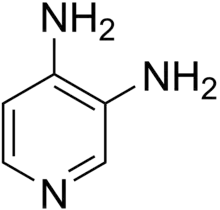

Three other treatment modalities also aim at improving LEMS symptoms, namely pyridostigmine, 3,4-diaminopyridine (amifampridine), and guanidine. They work to improve neuromuscular transmission.

Tentative evidence supports 3,4-diaminopyridine] at least for a few weeks.[11] The 3,4-diaminopyridine base or the water-soluble 3,4-diaminopyridine phosphate may be used.[12] Both 3,4-diaminopyridine formulations delay the repolarization of nerve terminals after a discharge, thereby allowing more calcium to accumulate in the nerve terminal.[4][5]

Pyridostigmine decreases the degradation of acetylcholine after release into the synaptic cleft, and thereby improves muscle contraction. An older agent, guanidine, causes many side effects and is not recommended. 4-Aminopyridine (dalfampridine), an agent related to 3,4-aminopyridine, causes more side effects than 3,4-DAP and is also not recommended.[5]